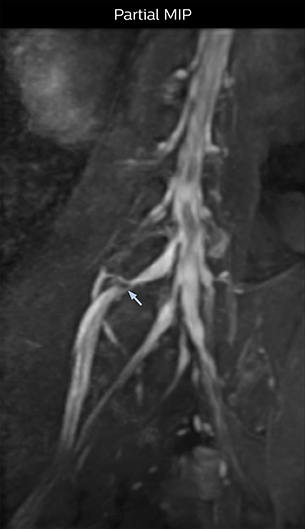

“In such case, we would then browse through axial T2-weighted MR images slice by slice and mentally reconstruct the actual situation based on both radiculography and MRI. Fortunately, NerveVIEW can now very well show nerve courses and presence of nerve compression or edema in one single image series.” “We have often seen NerveVIEW directly depict details of the nerve compression that were not observed by radiculography. Therefore, we think that with NerveVIEW we can reduce the number of invasive examinations, especially for some patients with lumbar plexus symptoms.”

“The intra-luminal signal of veins, especially around the intervertebral space, can be suppressed well with NerveVIEW. As a result, we can easily observe the detailed nerve structure around the posterior ganglion,” he says. “This is why we use 3D NerveVIEW for intraforaminal stenosis and extraforaminal stenosis/herniation (lateral disc herniation). On the other hand, if herniation is suspected to exist inside the dorsal root ganglion (DRG), balanced TFE or ProSet-FFE is applied. NerveVIEW is not suitable for evaluating the median type of herniation.” The SE-EPI DWI-based method for MR neurography works well for large FOV exams like whole-body MRI, but focal examination of nerves is often limited by the attainable spatial resolution (both inplane and slice direction) and geometric distortion. “3D NerveVIEW achieves higher in-plane resolution – close to our other routine spine sequences – and the source images can be used instead of adding a fat-suppressed T2-weighted sequence,” Tanji says.

According to Tanji, methods such as ProSet FFE, STIR or 3D VISTA are anatomically nonselective because background signals, for instance from blood vessels, often interfere with nerves, which hampers evaluation of details, especially at the peripheral side of the nerves.

“Recently, the two surgical methods extreme and oblique lateral interbody fusion (XLIF and OLIF) have become mainstream for minimally invasive treatment of lumbar spinal canal stenosis and intervertebral foramen stenosis. With these surgical techniques, the spine is approached from the flank, and prior knowledge of the exact anatomy of the lumbosacral plexus would be extremely helpful. To that end, high slice resolution (less than 1 mm acquisition) that enables sharper sagittal MPR images will be needed.”

“For both brachial and lumbar plexus, we are currently using a 230 mm FOV and voxels of about 1 x 1 x 2 mm acquired (1 x 1 x 1 mm reconstructed). This provides us a good representation of the nerves, even though this FOV is relatively small. Regarding the inplane resolution, we hope to be able to bring that down to 0.7 mm, similar to our typical 2D multislice T2W images,” says Tanji.